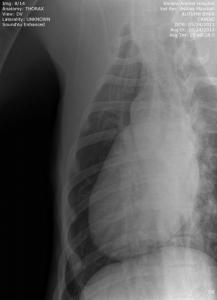

UPDATE: I know I have much to update in BHRR's Autumn's blog and before I go to bed in the wee hours; I shall update her blog plus add photos from her x-rays – taken of both legs, chest, back, legs, heart etc. on October 24th, 2012 and you can find them below! 🙂

From there, we are putting our creative hats on as she will need two cruciate surgeries – $6,000-$7,000+ – and the specialist is still looking at those eyes and what is going to be best….

She has three surgeries ahead of her – a spay and two separate cruciate surgeries and this is in addition to her almost $3,000 bills to date that have been racked up.